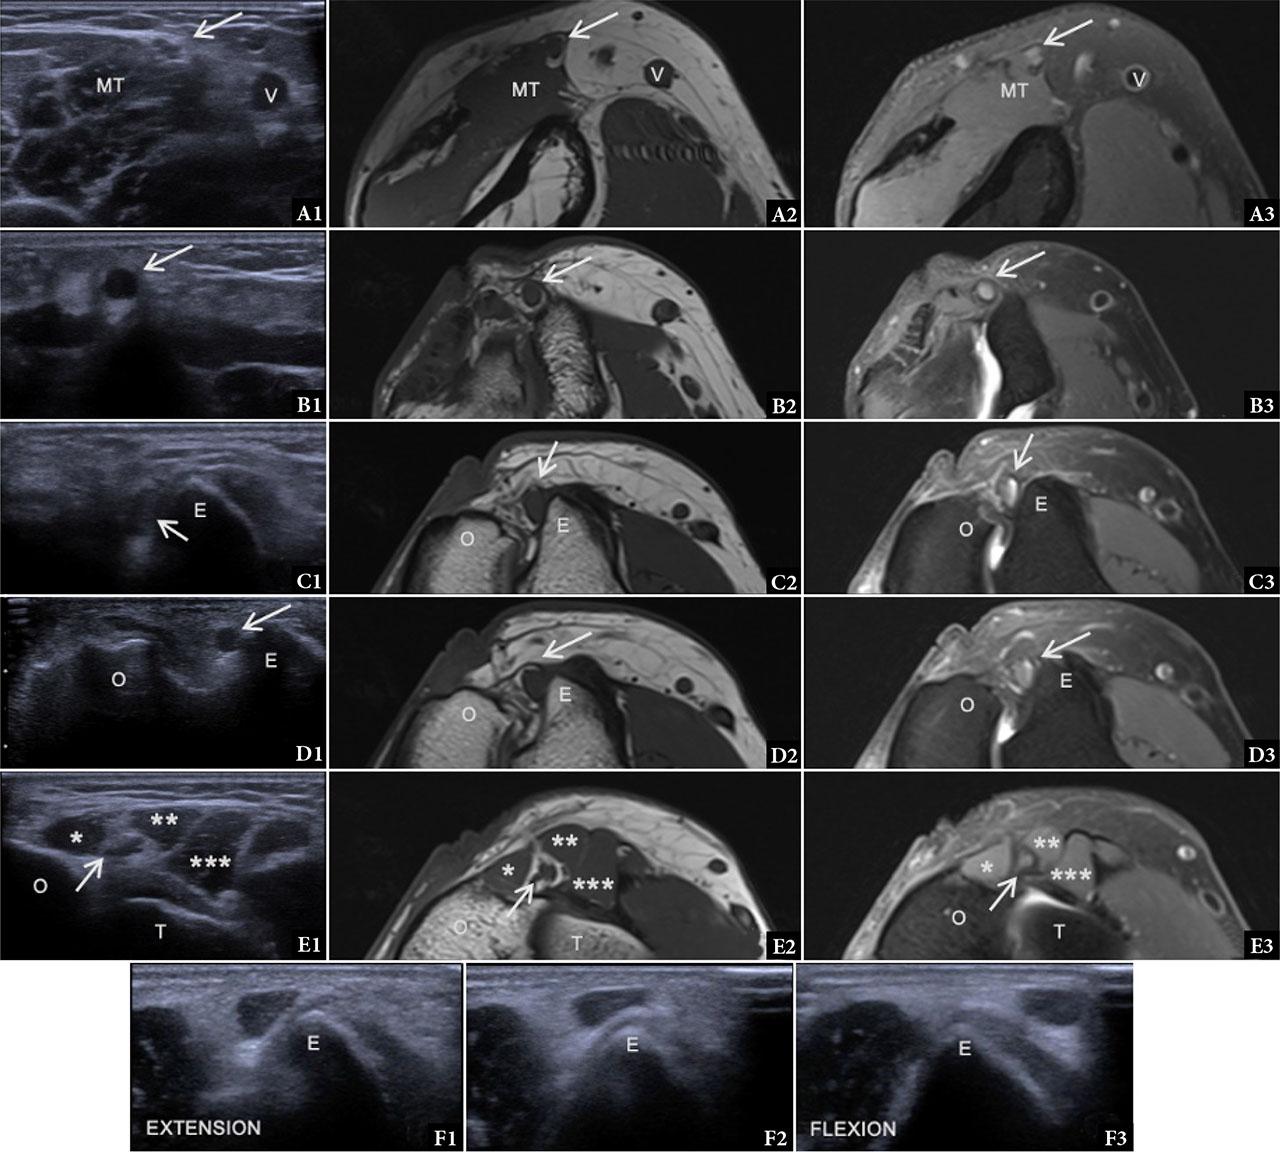

Ulnar nerve neuropathy due to instability. A–E. Proximal to distal axial images in a 55-year-old male patient with ulnar nerve neuropathy due to instability. Ultrasound axial images (first column); MRI axial T1 TSE images (second column); MRI axial PD FS TSE images (third column). A. Arcade of Struthers level: Normal ulnar nerve (arrow), medial head of triceps (MT), basilic vein (V). B–C. Retrocondylar groove level: Neuropathic ulnar nerve − hypoechoic on ultrasound and hyperintense on PD FS MRI. Medial epicondyle (E). D. Cubital tunnel level: Neuropathic ulnar nerve (arrow). Medial epicondyle (E), olecranon (O). E. Flexor carpi ulnaris (FCU) level: Normal ulnar nerve (arrow), olecranon (O), medial margin of humeral trochlea (T), ulnar head of FCU (*), humeral head of FCU (**), flexor digitorum superficialis (***). F. Ultrasound at the same level as (C) during dynamic assessment: F1. Elbow in extension, ulnar nerve in normal position; F2. Ulnar nerve luxation during elbow flexion; F3. Ulnar nerve displaced anteriorly at 90° elbow flexion

Ultrasound findings. With the elbow in extension, the normal nerve is oval and lies within the groove; during flexion, medial displacement or subluxation of the nerve can be dynamically visualized. In chronic cases, loss of fascicular detail and signs of perineural fibrosis may be evident(10).